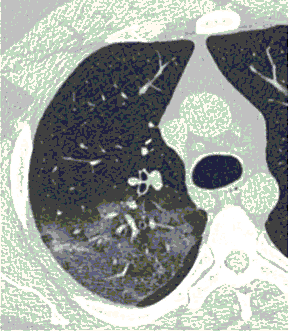

КТ имеет высокую чувствительность в выявлении изменений в легких, характерных для COVID-19. Применение КТ целесообразно для первичной оценки состояния ОГК у пациентов с тяжелыми прогрессирующими формами заболевания, а также для дифференциальной диагностики выявленных изменений и оценки динамики процесса. КТ позволяет выявить характерные изменения в легких у пациентов с COVID-19 еще до появления положительных лабораторных тестов на инфекцию с помощью МАНК. В то же время, КТ выявляет изменения легких у значительного числа пациентов с бессимптомной и легкой формами заболевания, которым не требуется госпитализация. Результаты КТ в этих случаях не влияют на тактику лечения и прогноз заболевания при наличии лабораторного подтверждения COVID-19. Поэтому массовое применение КТ для скрининга асимптомных и легких форм болезни не рекомендуется.

6. Внутривенное контрастирование при КТ у пациентов с известной/предполагаемой вирусной (COVID-19) пневмонией проводится при подозрении на заболевания и патологические состояния, диагностика которых невозможна без использования контрастных средств (ТЭЛА, онкологические заболевания др.). Внезапный рост концентрации Д-димера в анализах крови и клиническое подозрение на ТЭЛА являются важными критериями для выполнения КТ-ангиопульмонографии при условии, что ее положительный результат может оказать влияние на лечение и ведение пациента.

8. Рекомендовано проведение лучевого исследования пациентам с тяжелым и крайне тяжелым течением ОРИ, требующим лечения в условиях ОРИТ:

- оптимально: выполнение экстренного КТ исследования легких по стандартному протоколу без внутривенного контрастирования, если возможна транспортировка пациента в кабинет КТ до ОРИТ;